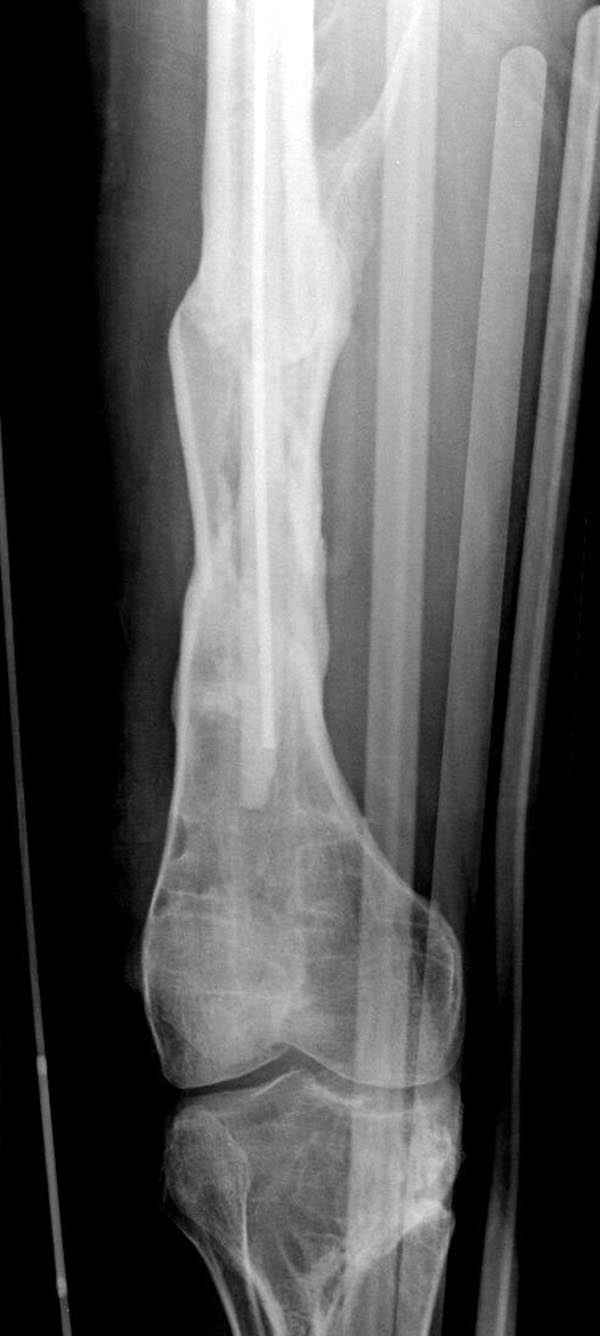

Представляю снимки больного с политравмой: леченного в другом мед.учреждении по поводу открытого перелома бедра, сперва аппаратом наружной фиксации, затем пластиной. Обратился к нам через 8 месяцев после удаления пластины с проблемой несросщего перелома бедренной кости, без клинических проявлении к инфицированию (не все снимки сохранены)

Рутинный интрамедуллярный остеосинтез с расверливанием и с фиксацией реконструктивным трокантерик штифтом (рис №1, №2),

если первые 4 месяца послеоперационного периода проходил без проблем, но на 5 месяце появились боли в дистальном отделе бедра и температура, т.е. симптомы медуллярного инфицирования (рис №3, №4).